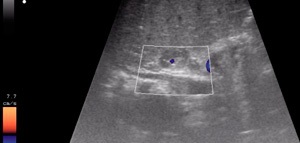

rinichi imagine cu ultrasunete si glandei suprarenale

O glanda suprarenală cu ultrasunete este, de asemenea, realizată, precum și alte organe retroperitoneale cu ultrasunete. Pacientul ia poziția culcat pe spate sau pe lateral. Burtă și talie este lubrifiat cu un gel special. După aceea există o ecografie direct, folosind un senzor special. Autoritatea a analizat în diferite proiecții. Rezultatele astfel imediat difuzate pe un monitor special.

Medicul efectuează diagnosticarea cu ultrasunete a glandelor suprarenale

Din păcate, determină glandele suprarenale nu este întotdeauna posibil. Suprarenală dreapta disponibil pentru vizualizare în 90% din cazuri, și a plecat la 50%. În cazul în care glanda suprarenala nu are modificari patologice, tesatura ei va avea aceeași ecogenicitatea ca și din jurul țesutului adipos.

În mod normal, glandele suprarenale nu sunt vizualizate. Că acestea sunt detectate doar în cazul în care există schimbări structurale în deteriorarea de organe și țesuturi începe să difere de rinichi din tesuturile inconjuratoare si glandele suprarenale. În cele mai multe cazuri, un tehnician calificat poate detecta întotdeauna modificări ale glandelor suprarenale.